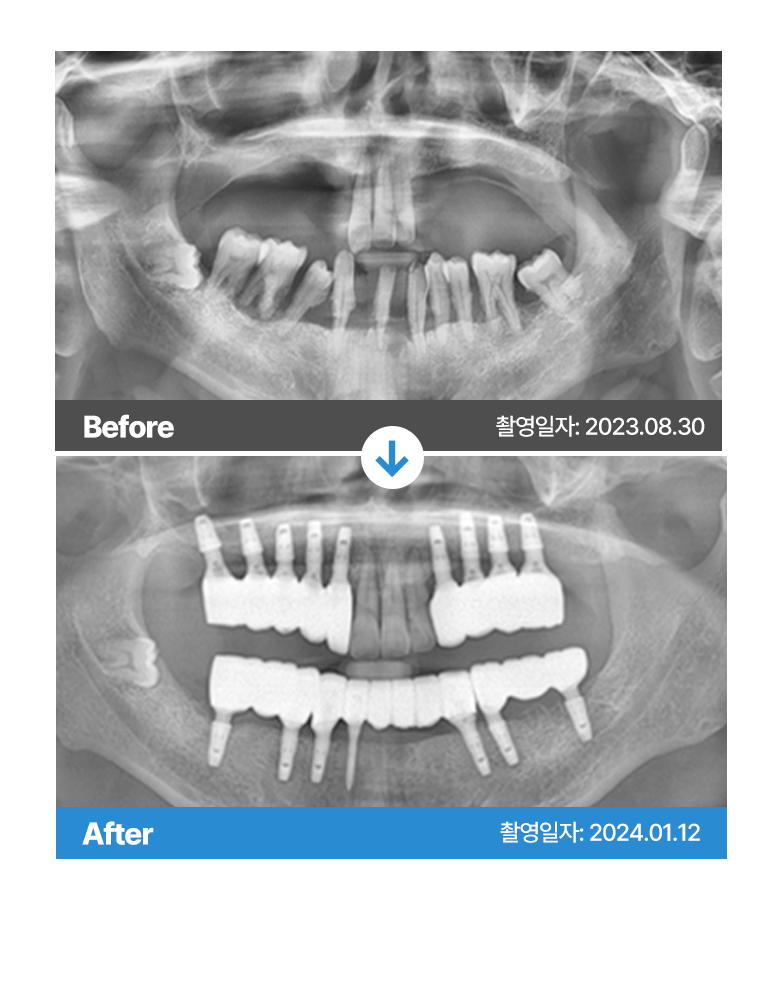

* 본원에서 치료 받으신 환자분의 사례로

환자분의 동의를 얻어 활용함을 안내드립니다.

개인에 따라 결과차이, 부작용 등이 발생할 수 있으므로

의료진과의 상담을 통해 신중히 결정하시기 바랍니다.

* 본원에서 치료 받으신 환자분의 사례로 2차적인 가공이 없으며, 환자분의 동의를 얻어 활용함을 안내드립니다.

개인에 따라 결과차이, 부작용 등이 발생할 수 있으므로 의료진과의 상담을 통해 신중히 결정하시기 바랍니다.